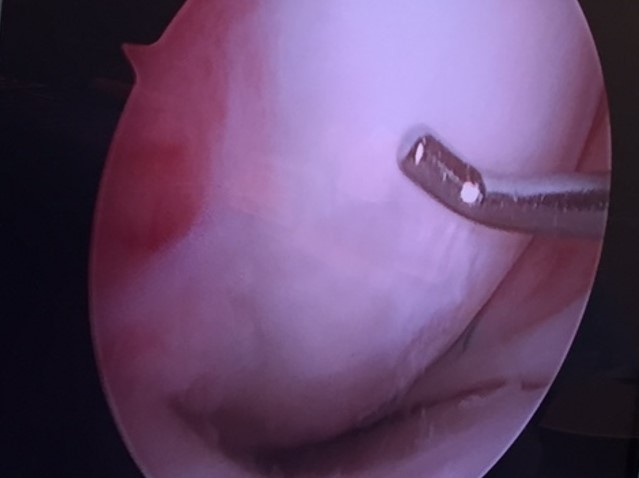

Placement of Cartiform

Four months after cartiform to femoral condyle